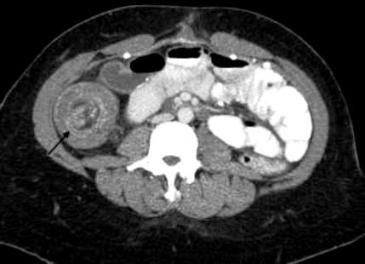

Figure 2 (click to enlarge)

A 30-year-old woman presented to the emergency department complaining of intermittent abdominal pain, nausea and vomiting, and passage of dark stool of several days’ duration. CT scan of abdomen and pelvis showed the terminal ileum “telescoping” through the ascending colon (Figure 1; Figure 2, arrows) confirming presence of ileocolic intussusception. A barium enema was attempted to reduce the intussusception but was only partially successful.